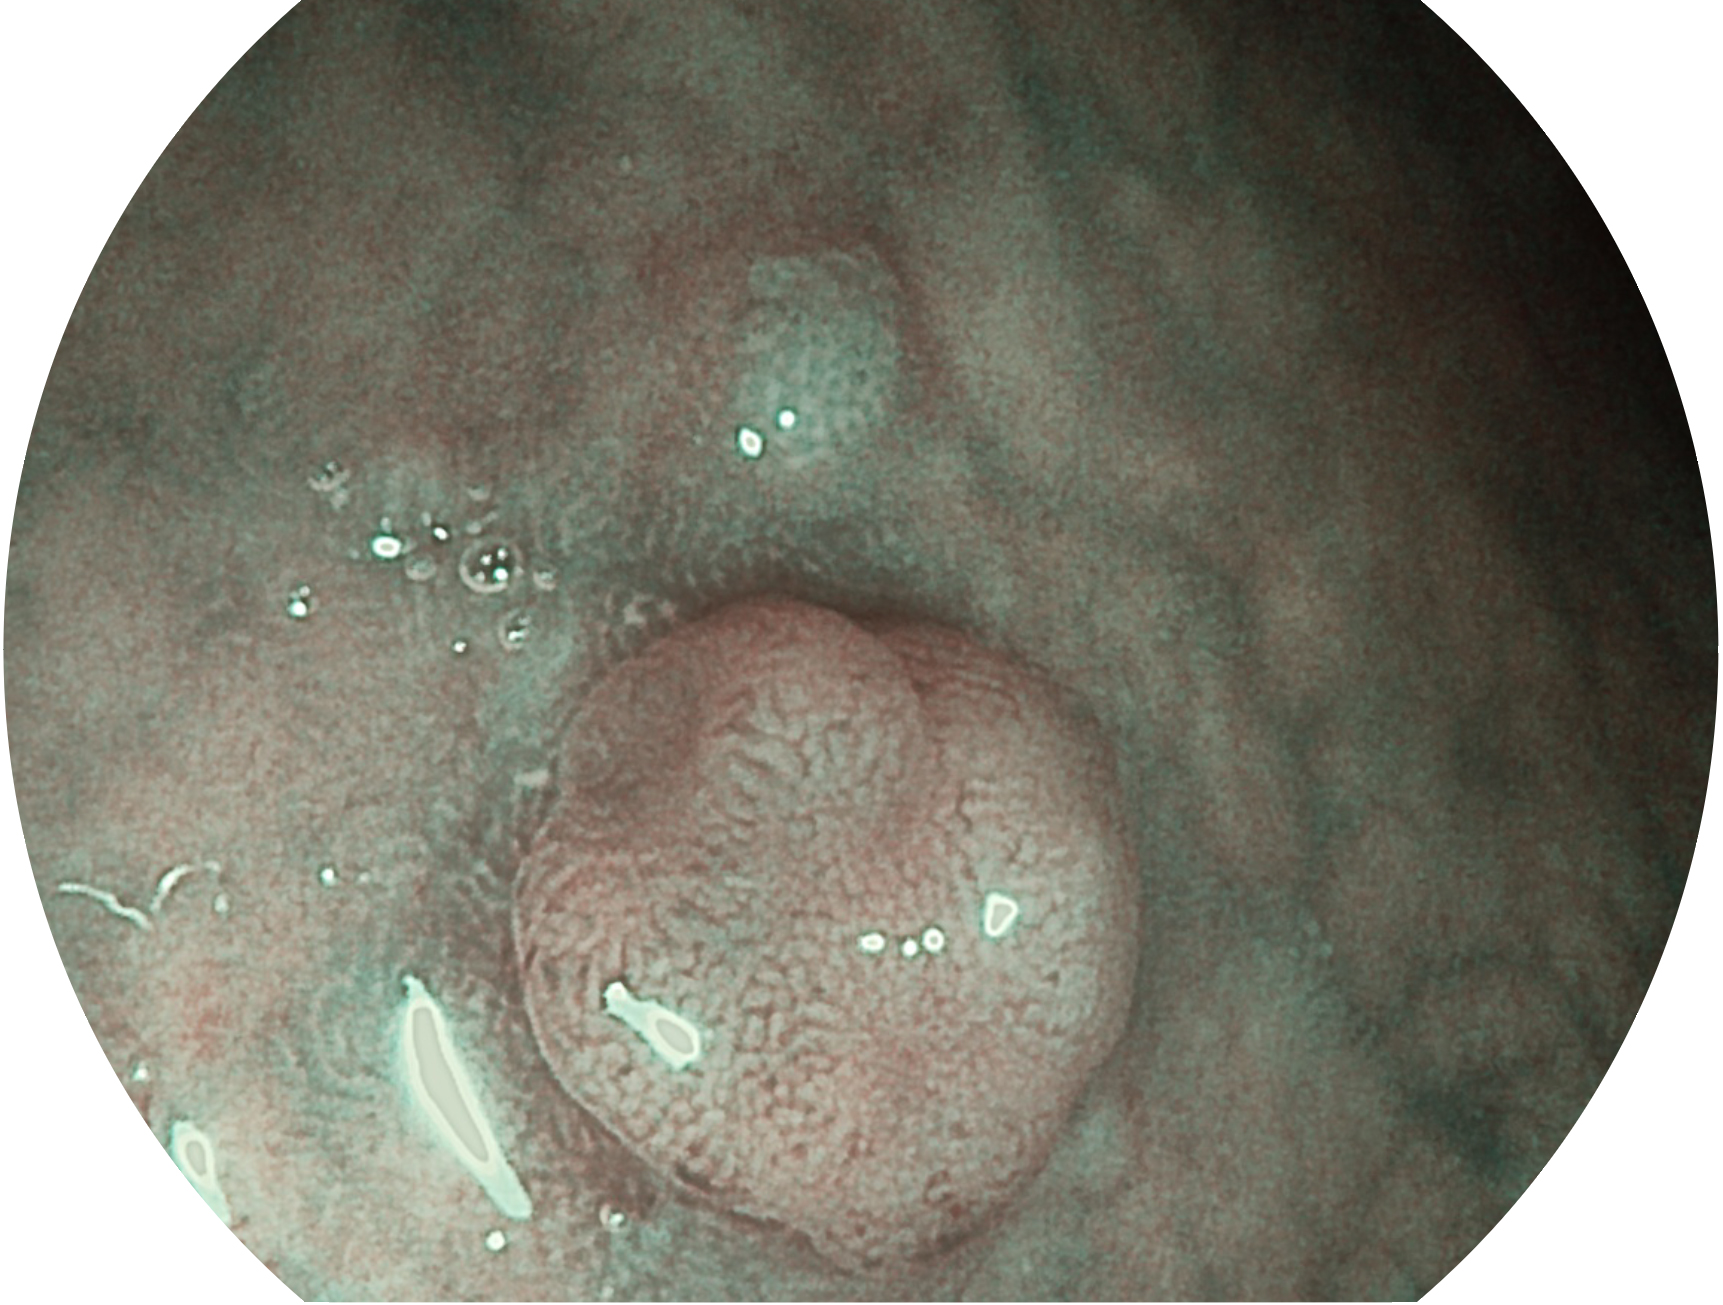

milan米兰新开发的内镜染色技术,主要是基于多波长LED 光源的开发,VLS-55Q 四波长LED 光源是由四个不同颜色的LED光按照相应照明模式所规定的特定发光比例进行合束后形成,合束后形成的照明光的光谱由红光、绿光、蓝光及蓝紫光这四个不同的波段范围构成。具有更高光谱自由度,通过光谱比例的控制,实现了聚谱成像技术,英文全称为“Spectral Focused Imaging, SFI”,缩写为“SFI”和光电复合染色成像技术,英文全称为“Versatile Intelligent Staining Technology, VIST”,缩写为“VIST”。